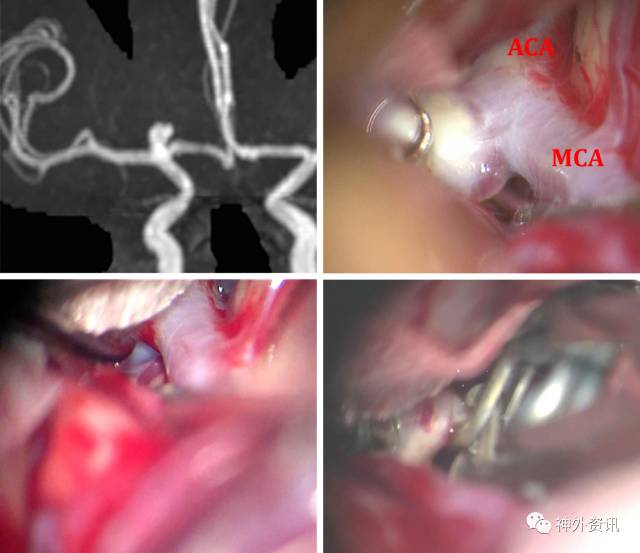

图2:右侧标本。在外侧裂蝶骨段的近端,床突上段ICA最终分为MCA的M1段和ACA的A1段,M1沿后外侧方向走形于侧裂里,A1则转向内侧并跨过视神经和视交叉。图片清晰显示了A1和M1近端发出的穿支动脉。